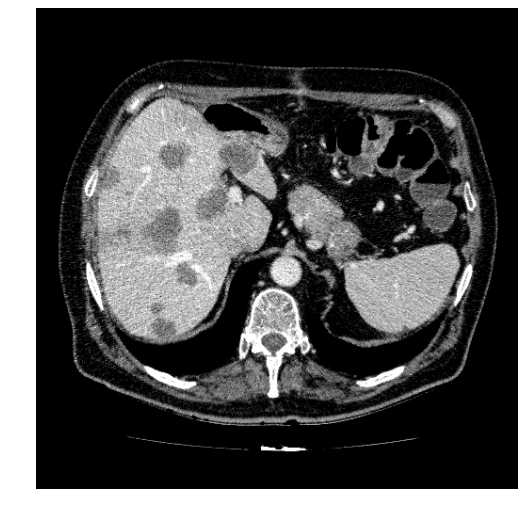

In clinical routine, manual or semi-manual segmentation techniques are applied to interprete CT and MRI images that have been acquired in the diagnosis of the liver. These techniques, however, are subjective, operator-dependent and very time-consuming. In order to improve the productivity of radiologists, computer-aided methods have been developed in the past. However, an automated robust segmentation of combined liver and lesion remains still an open problem because of challenges as a low-contrast between liver and lesion, different types of contrast levels (hyper-/hypo-intense tumors), abnormalities in tissues (such as after surgical resection of metastasis), size and varying number of lesions. As shown in figure 1 the heterogeneity in liver and lesion contrast is very large among subjects. Different acquisition protocols, differing contrast-agents, varying levels of contrast enhancements and dissimilar scanner resolutions lead to unpredictable intensity differences between liver and lesion tissue. This complexity of contrast differences make it difficult for intensity-based methods to generalize to unseen test cases from different clinical sites. In addition, the varying shape of lesions due to irregular tumor growth and response to treatment (i.e surgical resection) reduce efficiency of computational methods that make use of prior knowledge on lesion shape.

Figure 1: Liver and liver lesions slices in CT and diffusion weighted DW-MRI as well as the corresponding histogram for liver and lesions pixels in the respective modality. The shape, size and level of contrast vary for different lesions. As the histograms indicate, there is a significant overlap between liver and lesion intensities, leading to a low overall contrast.